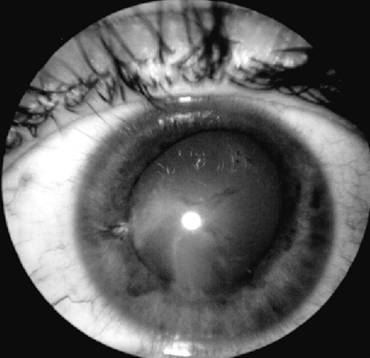

Iridodializa

PLANSA VI - TRAUMATISME OCULARE

dezinsertii la nivelul radacinii irisului (iridodializa-vezi plansa),

Iridodializa si recesia unghiului camerular se asociaza de regula de cresterea tonusului ocular.